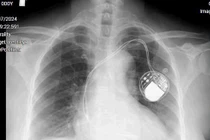

Máy tạo nhịp tim - Ảnh BSCC

Đây là một bộ máy điện tử nhỏ gọn, kích thước chỉ bằng mặt chiếc đồng hồ đeo tay, được cấy dưới da vùng ngực, kết nối với tim bằng 1 hoặc 2 dây điện cực giúp điều chỉnh, duy trì nhịp tim đều đặn.